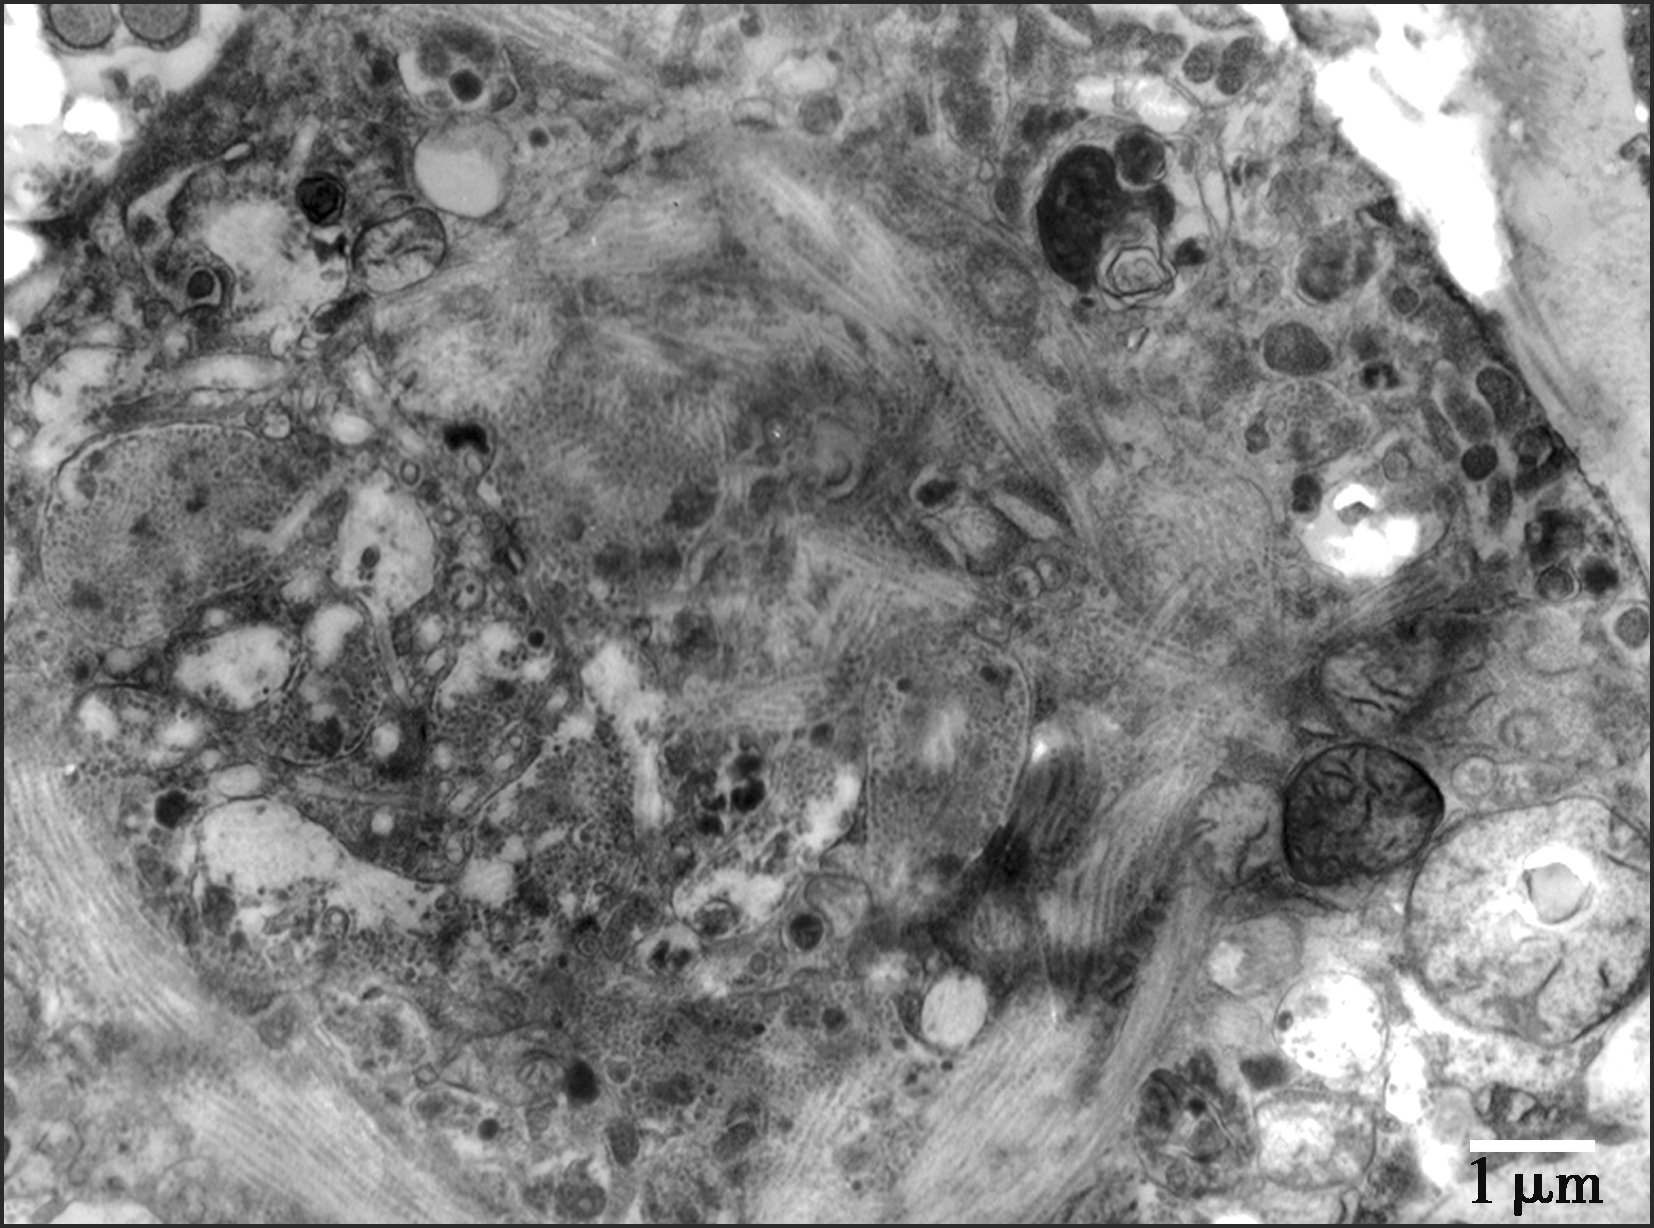

(七)超微结构

内膜肉瘤的超微结构特点符合肌纤维母细胞性分化,可见微丝、密体和不连续的外板(图3-3-11)。

图3-3-11 透射电镜示内膜肉瘤肿瘤细胞内含有大量微丝,符合肌纤维母细胞分化(TEM)